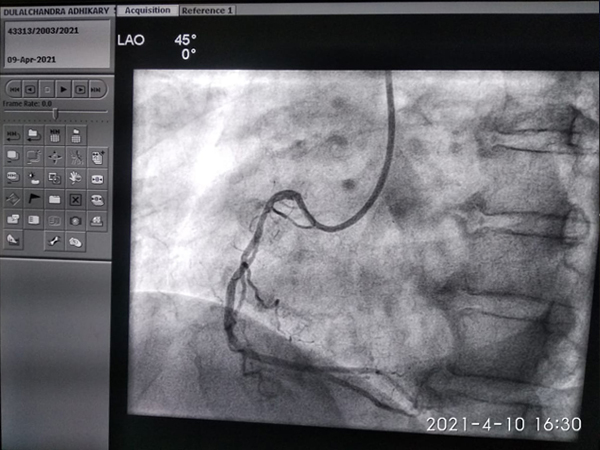

Subclavian vein intervention

Peripheral artery intervention

Device closure of post heart attack ventricular septal defect

Conduction system pacing physiological pacing

Cather directed Management of Deep vein thrombosis